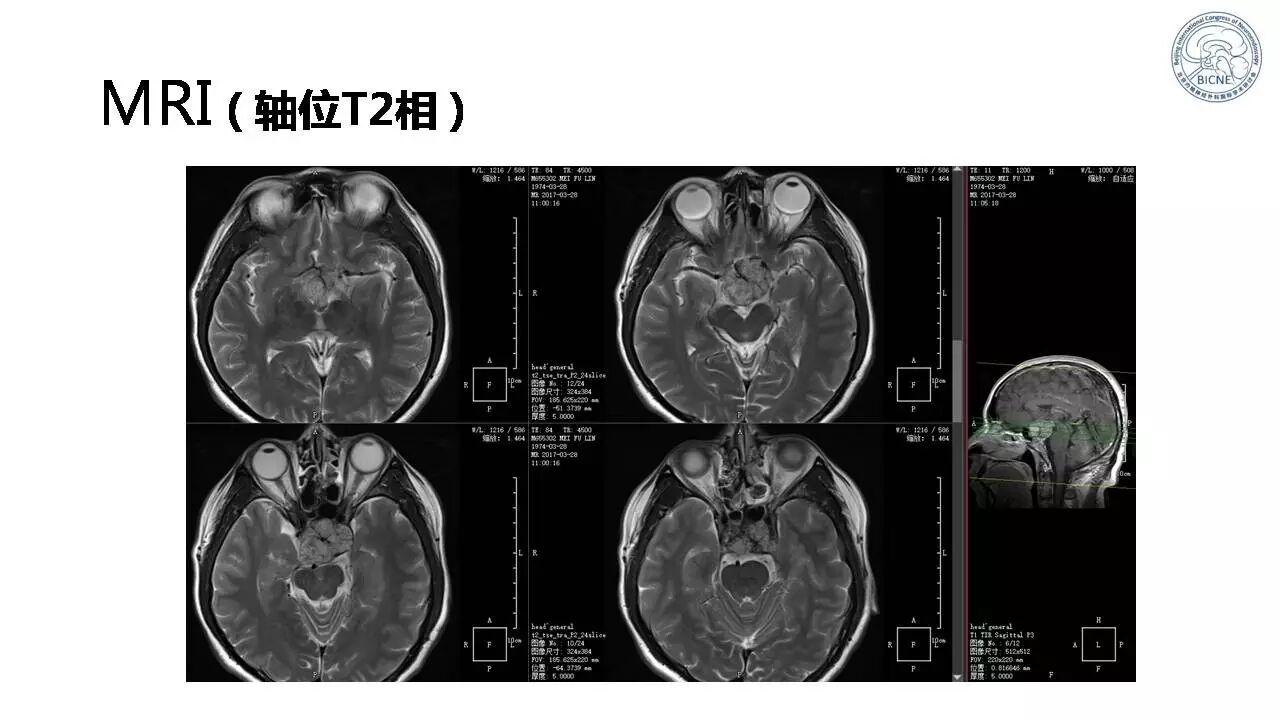

(三)王新生教授:鞍上蛛网膜囊肿脑室镜治疗

![]()